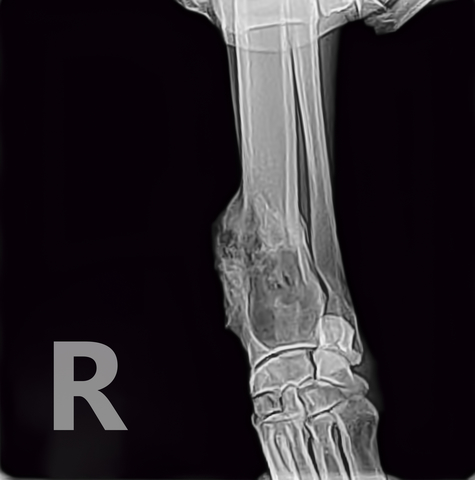

A lump or a bump, a wound that doesn't heal, any kind of swelling, enlarged lymph nodes, a lameness or swelling in the. Osteosarcoma is the most common primary bone tumor of dogs and nearly 10,000 dogs are diagnosed with this cancer each year. The dog cancer diet, full spectrum cancer care step 5: Most dogs will show signs of swelling and soreness in limbs close to joints. Chondrosarcoma is a malignant form of bone cancer in dogs characterized by a tumor of neoplastic chondroid and fibrillar matrix forming in cartilage.

Tales from the Dark Side from 2.bp.blogspot.com Staging of cancer helps your veterinarian identify if the cancer has spread to other locations in the body, which can change both the prognosis and appropriate treatment plan. The most import thing to remember about what to expect with bone cancer is that as long as your dog is not showing inward (or outward) signs of cancer, they will have a better chance of living a longer, healthier life and beating the bone cancer odds once the affected limb is removed. They will talk you through the various options, depending on the type of cancer your dog has. If the cancer develops in the legs, as it does in most cases, the usual course of treatment is amputation. You should keep a close eye on your dog to see if they are experiencing: Please do not let your dog suffer. The warning signs of cancer in dogs are very similar to that in people. Osteosarcoma is the most common primary bone tumor of dogs and nearly 10,000 dogs are diagnosed with this cancer each year.